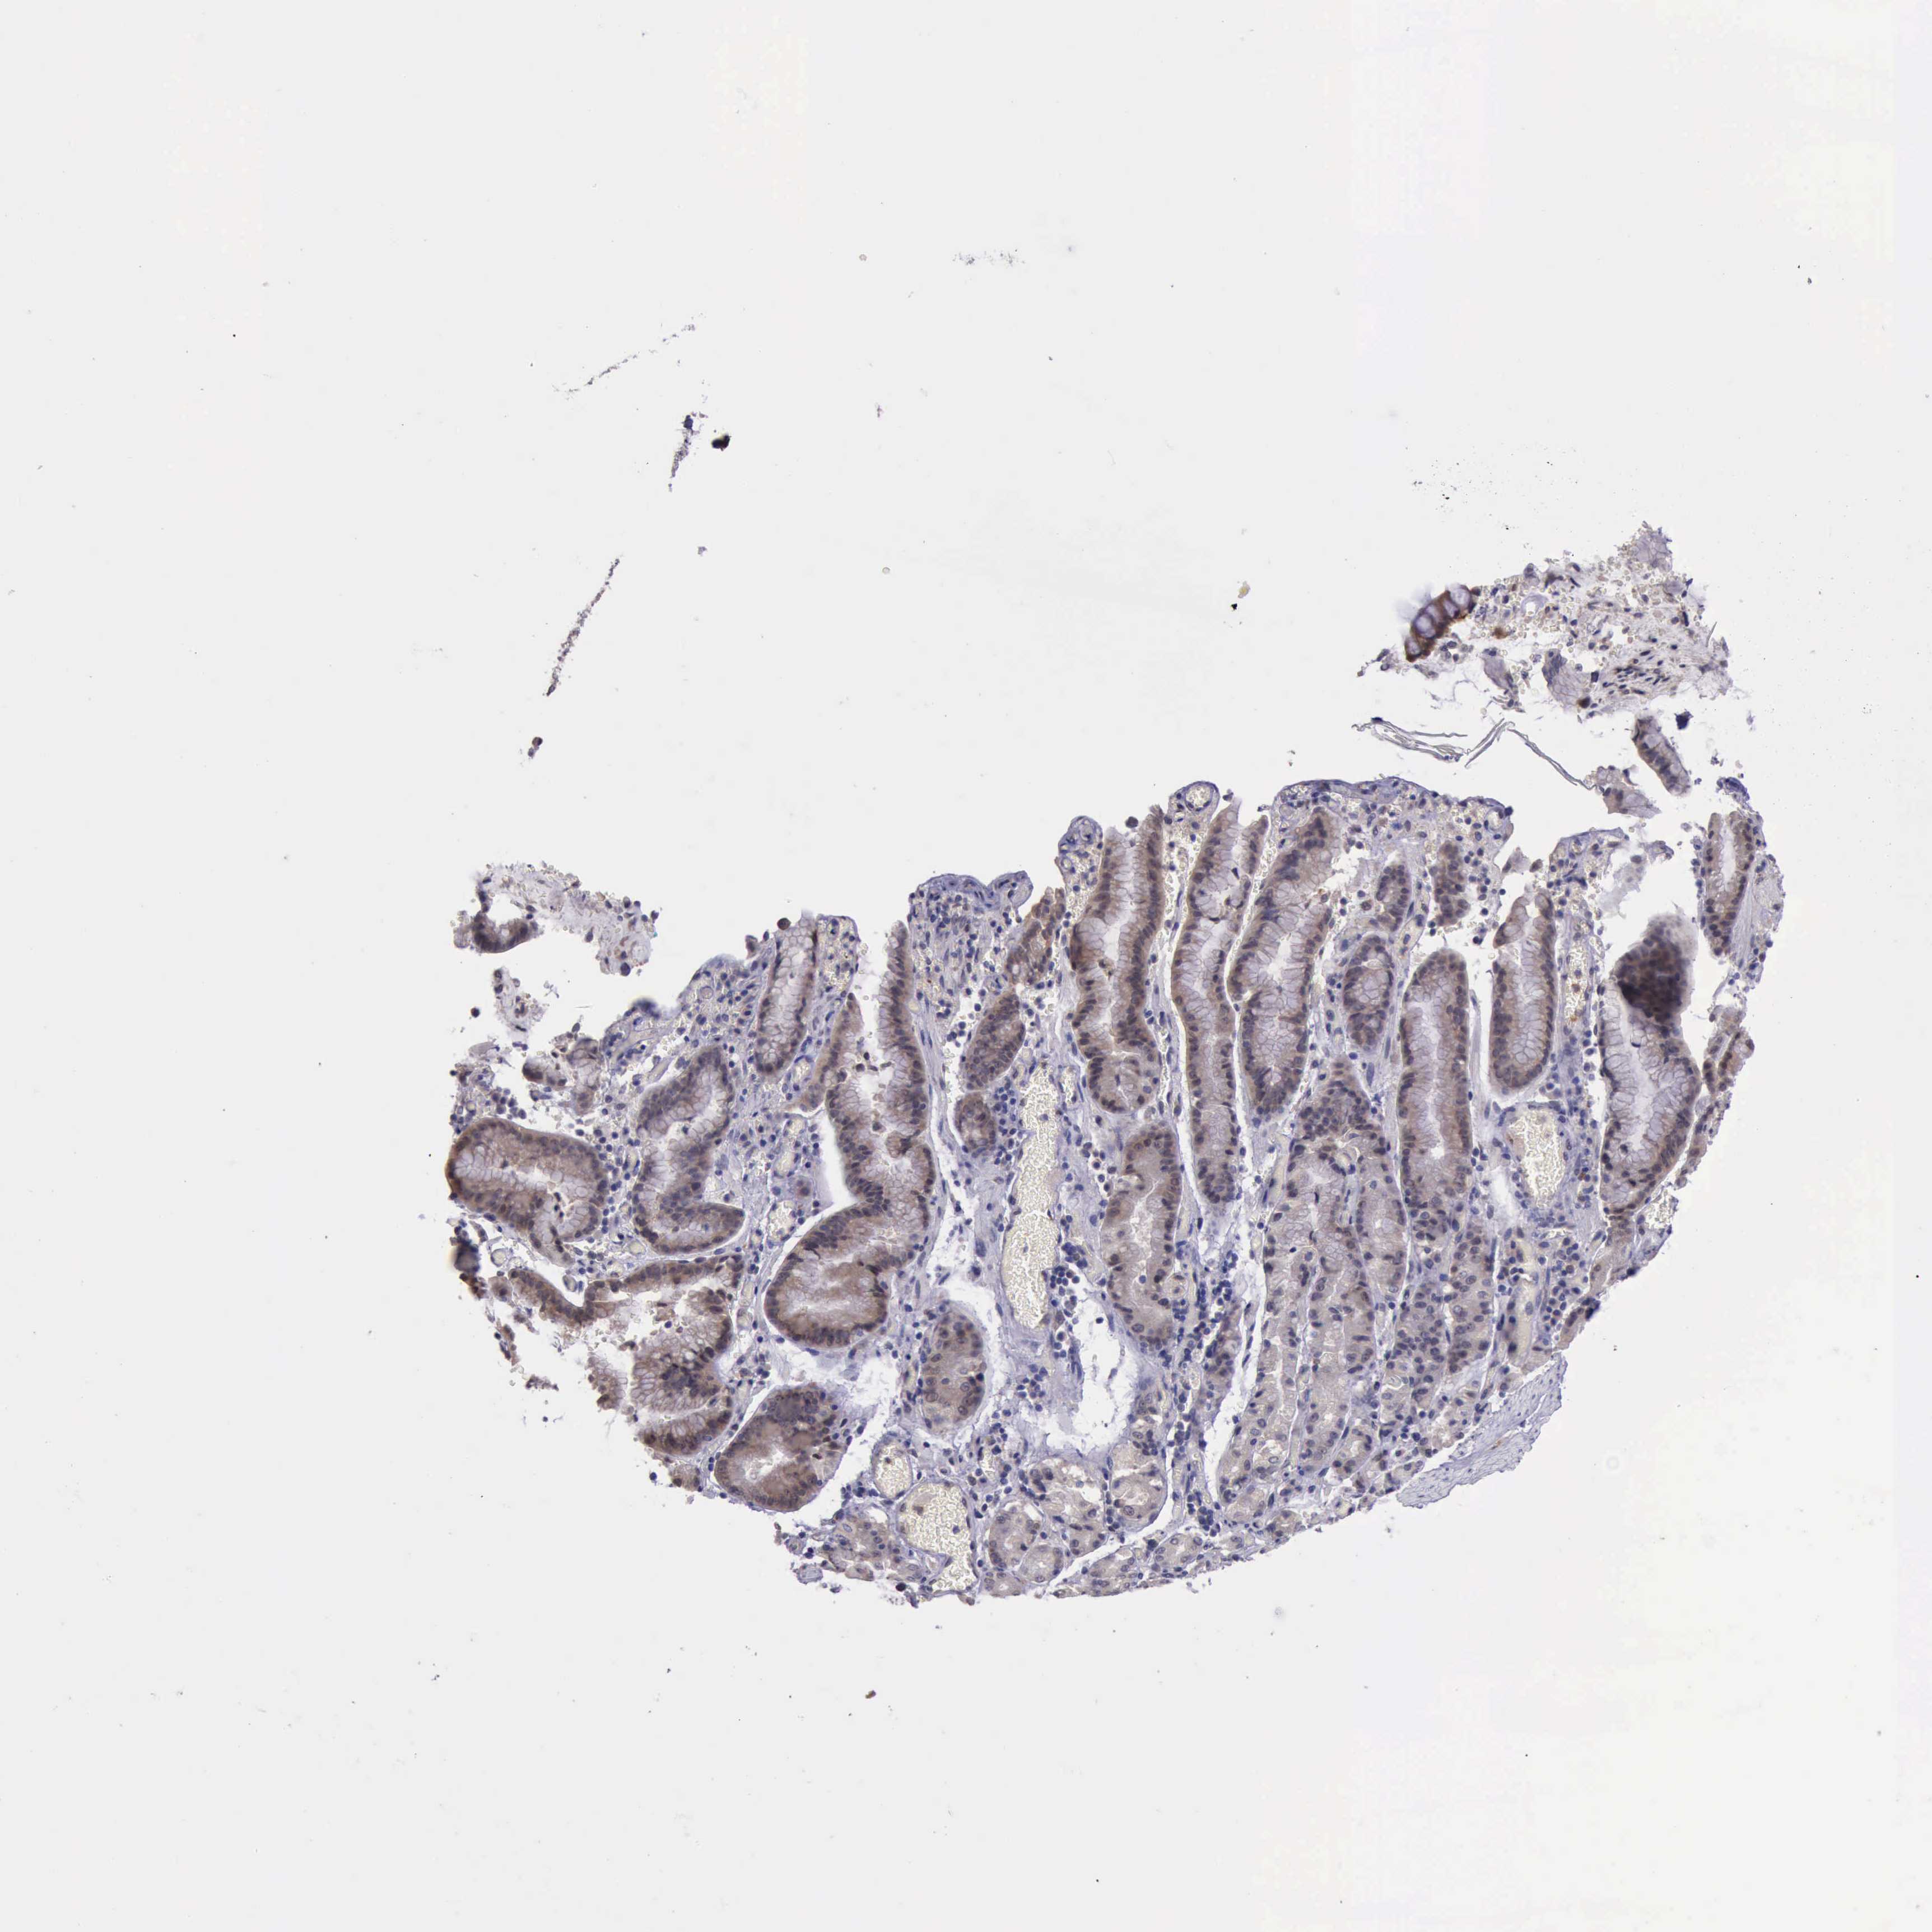

STOMACH CANCER - Protein expressioni

A mouse-over function shows sample information and annotation data. Click on an image to view it in a full screen mode. Samples can be filtered based on level of antibody staining by selecting one or several of the following categories: high, medium, low and not detected. The assay and annotation is described here.

Antibody stainingi

Antibody staining in the annotated cell types in the current human tissue is reported as not detected, low, medium, or high, based on conventional immunohistochemistry profiling in selected tissues. This score is based on the combination of the staining intensity and fraction of stained cells.

Each image is clickable and will lead to virtual microscopy that enables deeper exploration of all samples and also displays staining intensity scores, fraction scores and subcellular localization as well as patient and tissue information for each sample.

Antibody HPA001208

Staining

High

Medium

Low

Not detected

Intensity

Strong

Moderate

Weak

Negative

Quantity

>75%

75%-25%

<25%

None

Location

Nuclear

Cytoplasmic/membranous

Cytoplasmic/membranous,nuclear

Adenocarcinoma, NOS